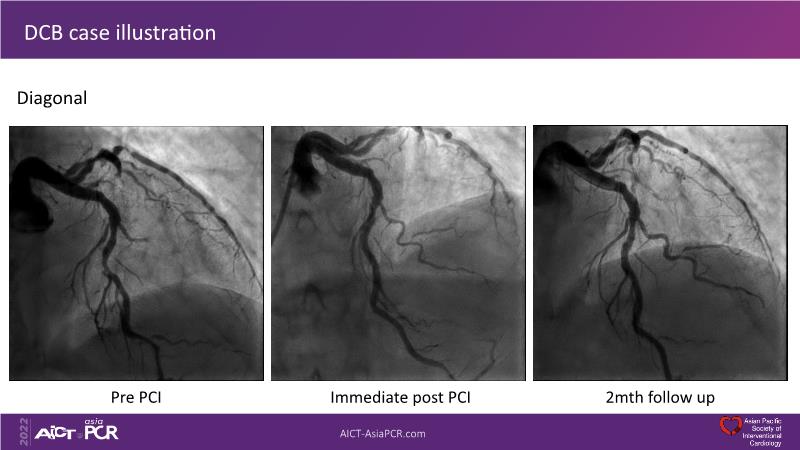

Sirolimus coated balloon: expanding the scope of coronary artery disease treatment

Consult this session to understand the technology and scientific evidence of the novel sirolimus drug-coated balloon, to learn its utility for PCI in a variety of lesion and patient subsets and to understand the evidence and outcomes in real-world patients.

- To understand the technology and scientific evidence of the novel sirolimus drug-coated balloon (SDCB)

- To learn the utility of the DCB for PCI in a variety of lesion and patient subsets

- To understand the evidence and outcomes of this DCB in real world patients